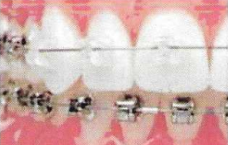

ΑΚΙΝΗΤΟΙ ΜΗΧΑΝΙΣΜΟΙ

Προσφέρονται για ακριβή, τρισδιάσταση και πολύπλοκη οδοντική μετακίνηση.

Αυτόδετα μεταλλικά

Αυτόδετα κεραμικά

Κλασσικά μεταλλικά ή κεραμικά